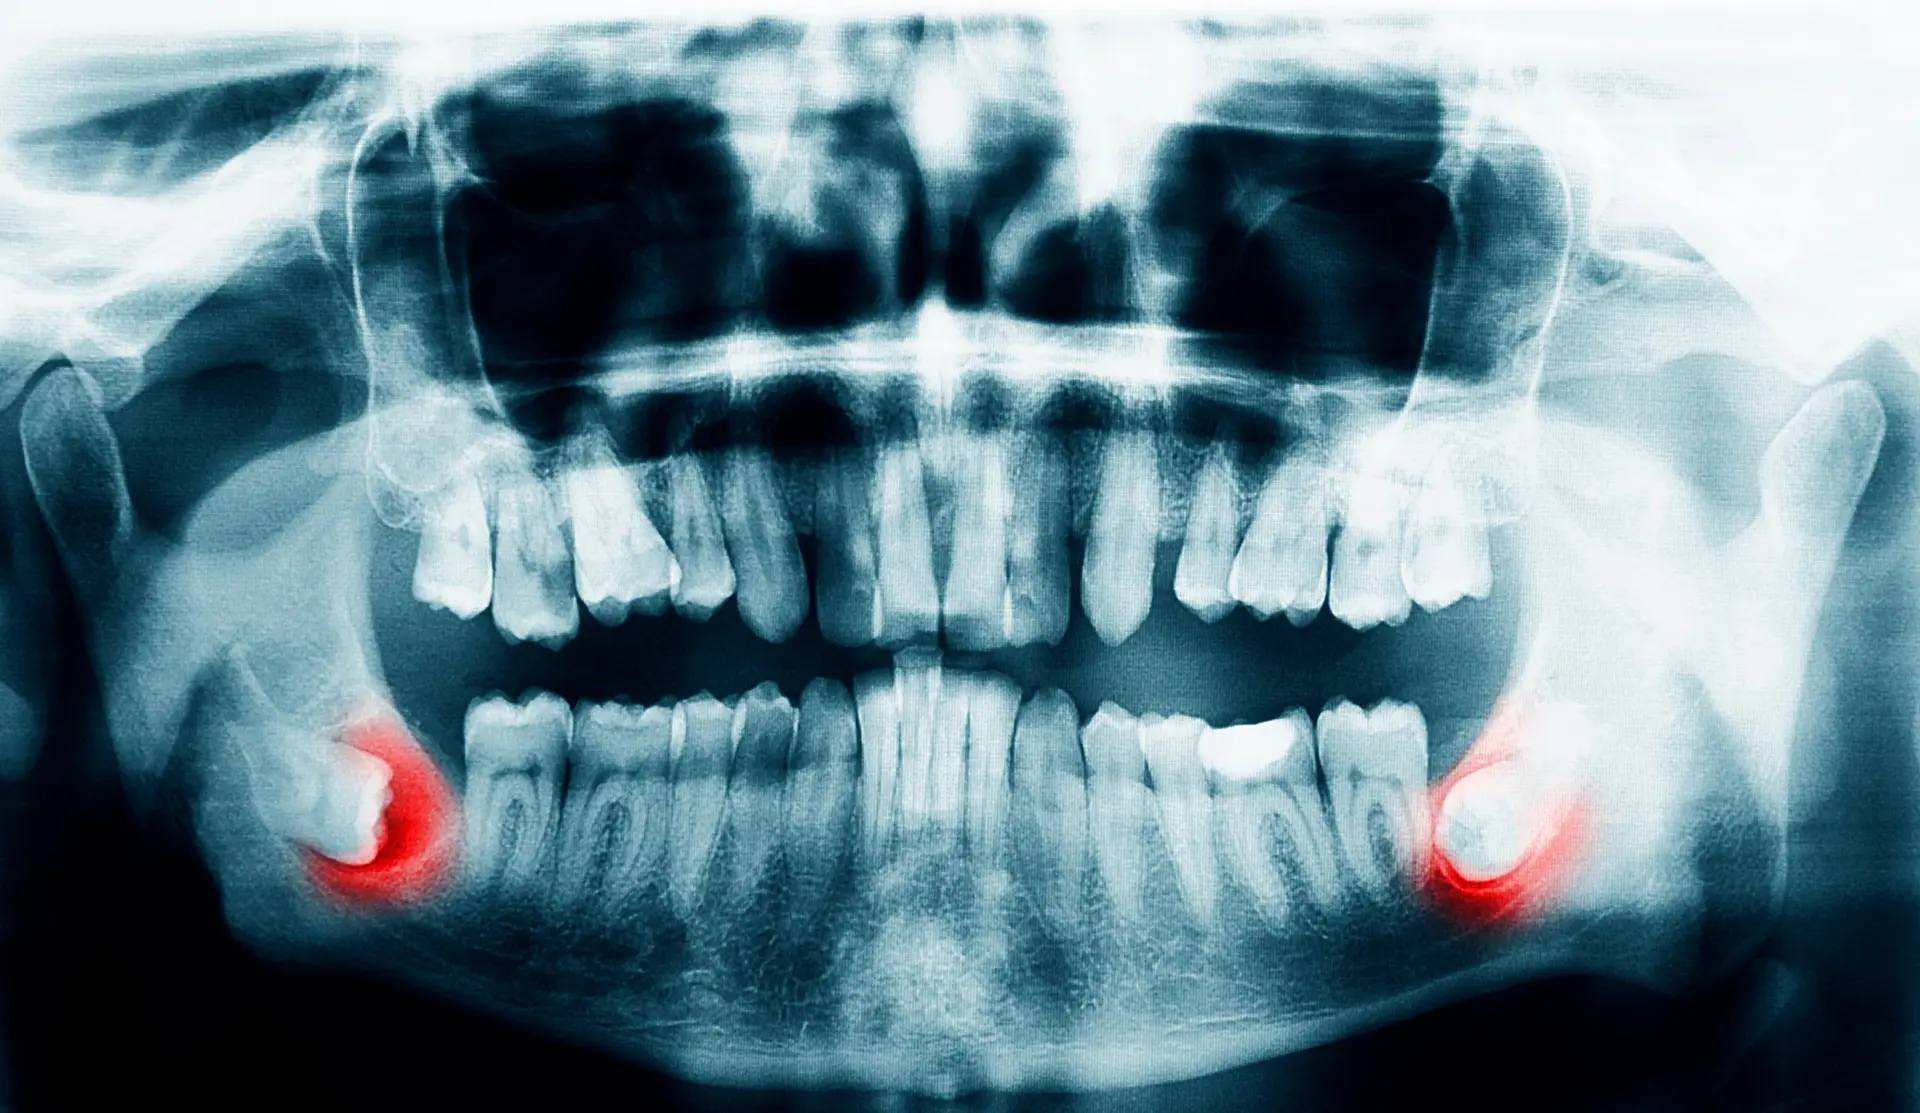

While not always harmful, it is often recommended for wisdom teeth to be extracted. When wisdom teeth are impacted or partially erupted, they do not provide any function but may cause significant harm to adjacent tooth and the jaw bone. Their eruption may cause dental crowding and misalignment of other teeth. They also encourage bacteria to accumulate in the pockets of your gum, putting you at risk for gum disease, infection, and tooth decay. Lastly, they may lead to cysts and tumors of the jaw that are locally destructive.

Our treatment plan will be determined based on your medical history and any relevant x-rays taken from your general dentist. We may need to take additional x-rays to ensure we have a complete view of your oral health. We will then create a personalized plan tailored to your unique needs and go over sedative options for maximum comfort.

There are many reasons why wisdom teeth removal may be necessary. This includes wisdom teeth growing in at the wrong angle. They can grow sideways, partially erupt, or even become trapped underneath the gum and bone. Impacted wisdom teeth can take many positions in the bone as they try to find a pathway to successfully erupt. All of these reasons make wisdom teeth removal necessary to preserve your oral health.